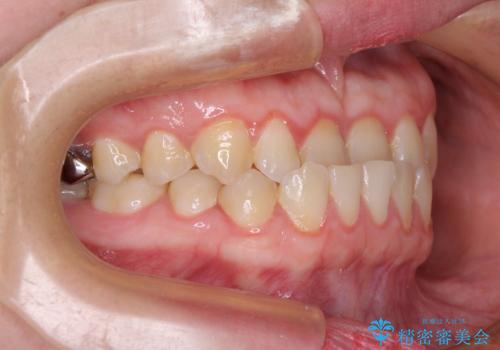

- 前歯の反対咬合を気にして来院された患者様です。

当院にて同様の咬み合わせを治療した方からのご紹介ということもあり、ご紹介者と同じワイヤー矯正で早めに治療を終えることを希望されました。

骨格的に下顎が前方に位置していましたが、歯列矯正で改善できると判断し、ワイヤー装置にて矯正治療を行うこととしました。